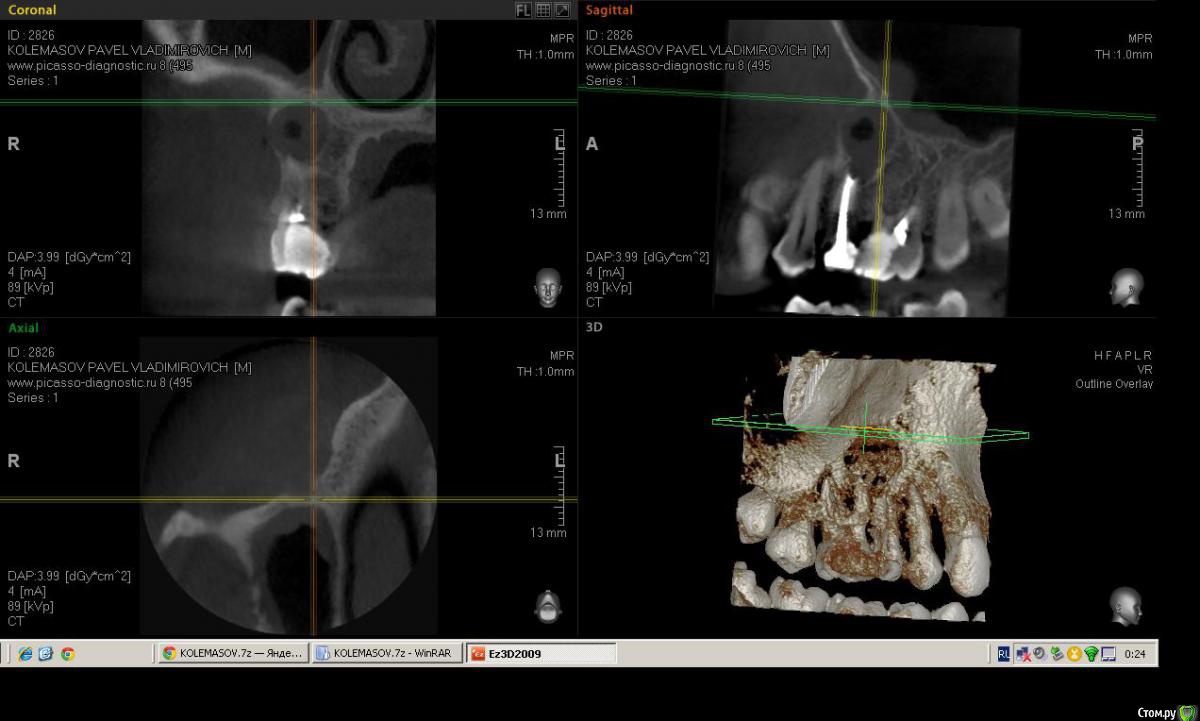

Salma Опубликовано 14 февраля, 2015 Поделиться Опубликовано 14 февраля, 2015 Пациент пришел с ноющими жалобами в области верхней челюсти справа, спасался обезболивающим несколько дней, говорит периодически болит, но сейчас разболелось сильно. Записался на вечер, на прием уже пришел немного припухшим. В полости рта, 16 зуб с глубокой полостью, перкуссия слабоболезненна, отечность болезненность по переходной, при надавливании выделяется гной, на небе в проекции верхушки небного корня тоже как бы формирующийся свищ с отделяемым. Делаем снимок прицельный, вижу разрежение в области 5-ки ( по словам пациента лечен более 10 лет назад). ДОговариваемся, что сегодня снимаем острую боль, а далее пациент делает кт и определяемся с судьбой зубов.Анестиеия, мех, мед,кальций. Делаю поласбляющий разрез, гной, нехило так проваливаюсь, кюретаж, дренаж. Собственно кт: (могу выслать ссылку на почту с кт) Ссылка на комментарий